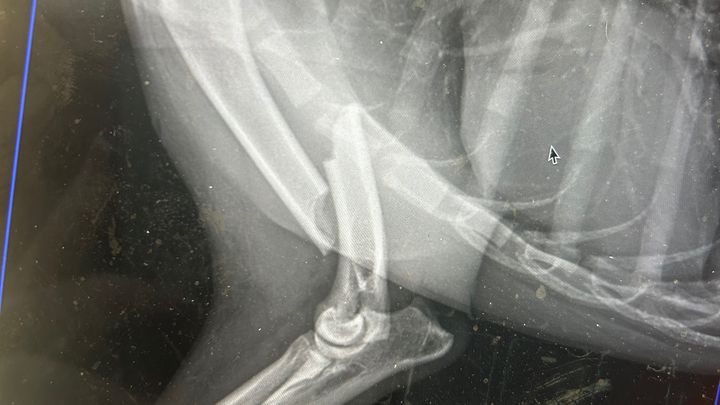

Yesterday, one of our pups, Cali, that we are working to adopt to her forever home, was kicked by a horse. She has a very clean but severe break in her shoulder and will require surgery! However, this surgery is approximately $6000, possibly more depending on the severity of the surgery, and there is no denying it, we just don't have it.